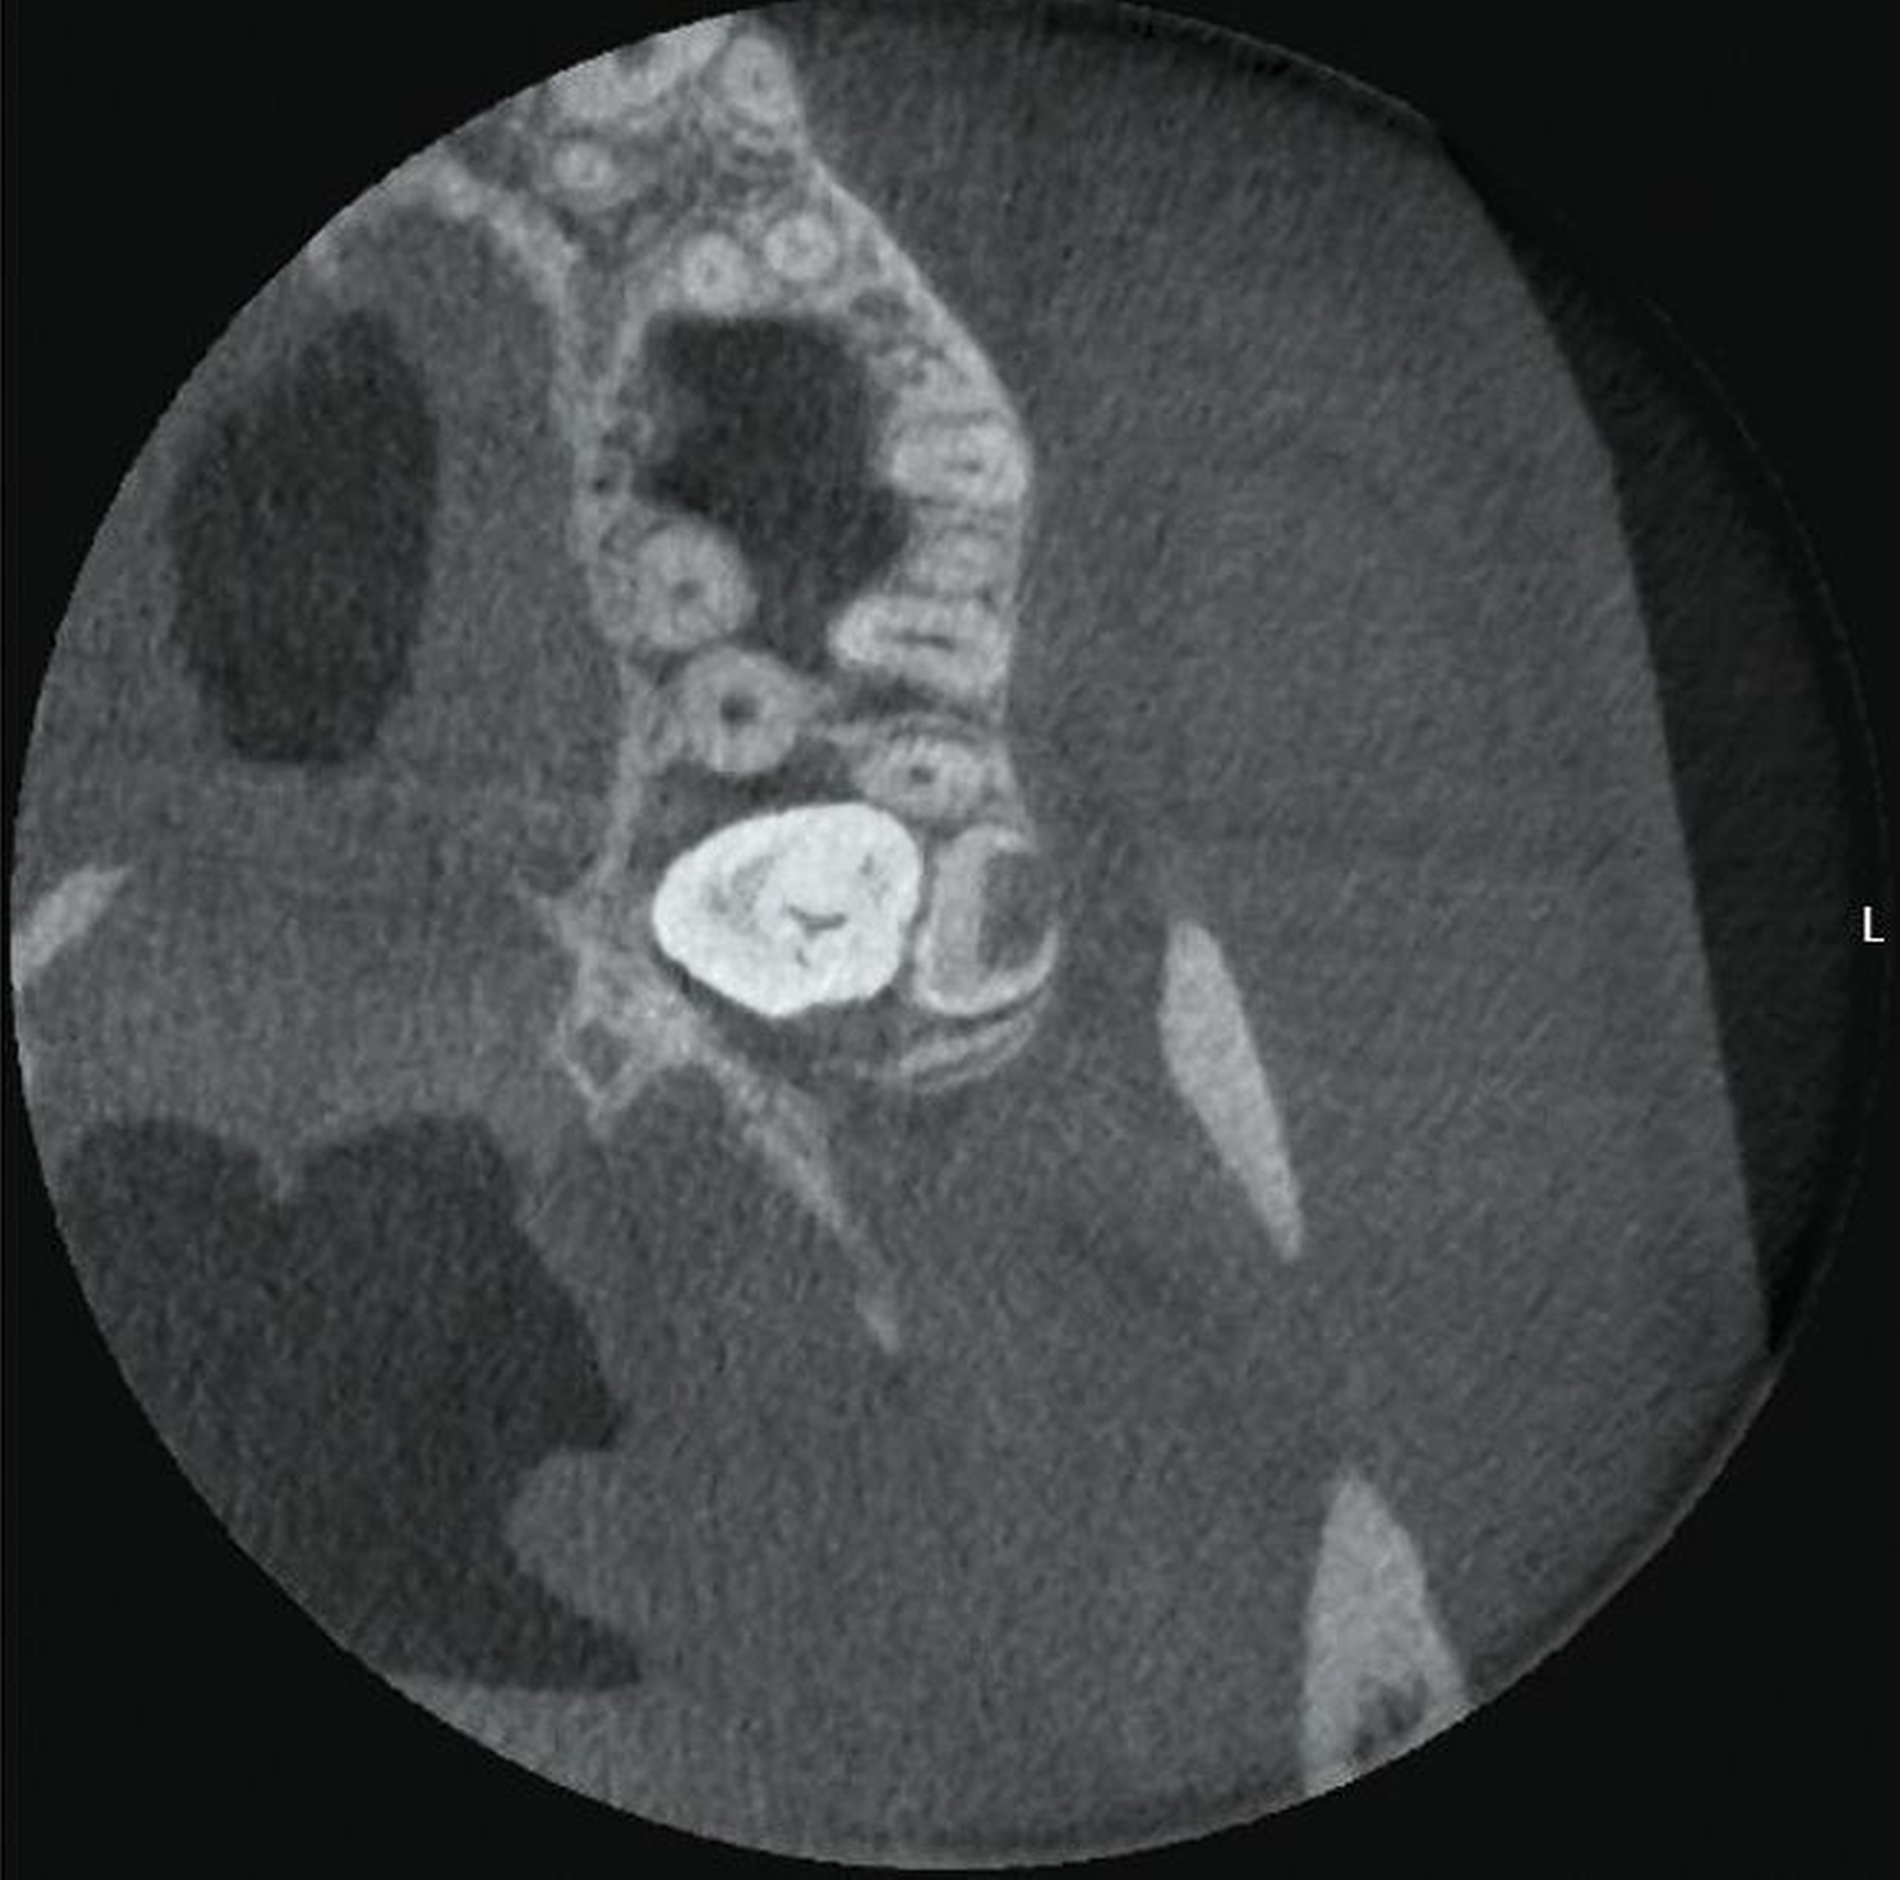

Im vorliegenden Fallbeispiel wurde eine dreidimensionale Bildgebung durchgeführt, da sowohl im Ober- als auch im Unterkiefer Risikohinweise bestanden. Zum einen lag eine unmittelbare Lagebeziehung zum N. alveolaris inferior und somit ein erhöhtes Risiko einer Nervschädigung vor, zum anderen bestanden Hinweise auf Lageanomalien und mögliche Doppelanlagen im Oberkiefer, die in der zweidimensionalen Bildgebung kaum beurteilt werden konnten. In der DVT zeigte sich in Regio 48 ein intraradikulärer Verlauf des N. alveolaris inferior durch die Wurzel des nach mesial gekippten und retinierten Zahnes 48 sowie eine perikoronare Aufhellung, die nah an die distale Wurzel des Zahnes 47 reicht (Abbildung 2).